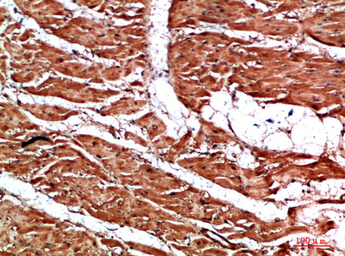

IHC-P analysis of human heart tissue using GTX34284 Titin antibody.

Dilution : 1:200